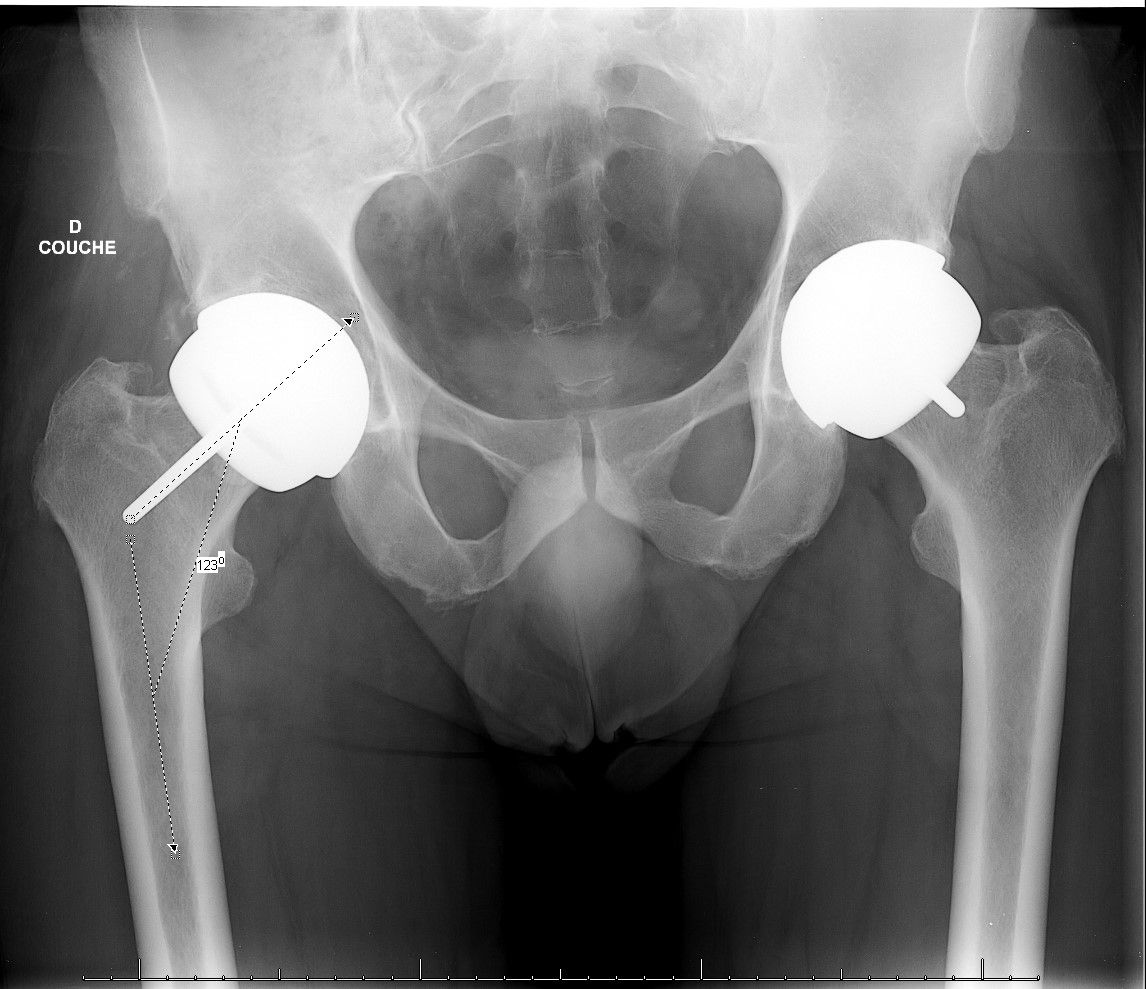

All patients underwent a preoperative and final clinical evaluation including Devane, Postel Merle d'Aubigné (PMA) and Harris Hip Score. Global and sectoral joint ranges were recorded. Radiographic analysis was performed on a front view of the pelvis, with the limb internally rotated by 15 to 20°. Interpretation and reproducibility of the radiographic analysis between the postoperative and preoperative films was ensured by measuring pelvic tilt and rotation. Criteria for reproducibility of the images were used with the tip of the coccyx, which was considered centred if it was located between 2 and 4 cm from the pubic symphysis. This ensured that there was no significant variation in version and/or pelvic tilt. The neck/shaft angle was measured between points C, C', and D, where C is the centre of the femoral head, C' is the middle of the neck, and D is the middle of the femoral shaft. The femoral offset was measured as the perpendicular to the femoral shaft axis through point C. The Stem Shaft Angle (SSA) was measured on the recoil films by considering the axis of the femoral implant in relation to the cervical axis. If the implant was deviated from the femoral neck, this was indicated by a + in degrees (°), and if it was deviated, by a - in °.

The mean preoperative neck/shaft angle was 120.9° [114.7-125]. The mean femoral offset decreased from 53.8 mm [40.9-75] preoperatively to 52.3 mm [40-70] at follow-up, and this difference was not significant (p> 0.05, Table 2).

The femoral offset was thus reduced by an average of 1.6 mm (6.7/-7.8), without this reduction being significant. The SSA angle at follow-up was 131.3° [118-134]. The mean valgus gain of the femoral implant compared to the native CCD bone angle was 8.7° (-4.6/14.8) (p<0.0001). Compared to preoperative data, four patients were elongated by less than 5 mm. No dislocations or thromboembolic events were observed. No hips were revised at the longest follow-up and we did not observe any Adverse Reaction to Metal Debris complications.